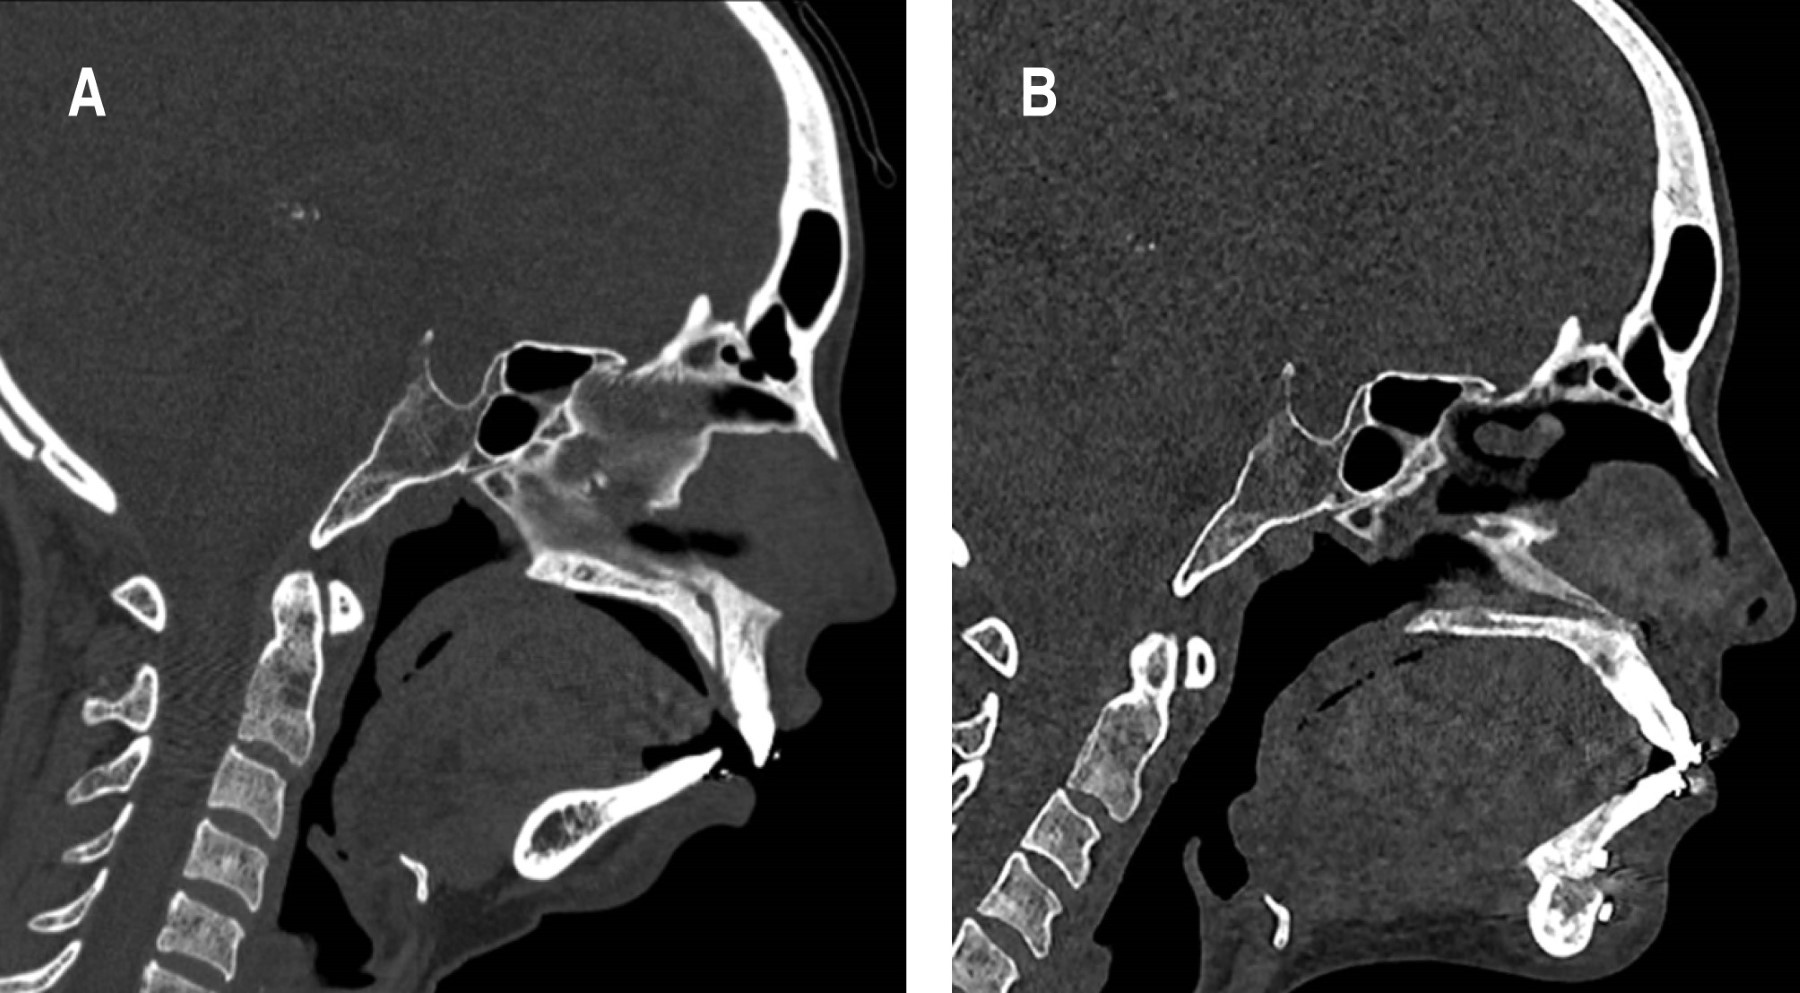

Se realiza tomografía computada que revela micrognatia asociada con aplasia de los cóndilos mandibulares con aplanamiento bilateral de las cavidades glenoideas y ausencia del tubérculo articular en su porción medial acompañado de luxación bilateral (Figura 2). Adicionalmente se realiza polisomnografía, la cual no evidencia alteraciones, descartando la posibilidad de síndrome de apnea obstructiva del sueño (SAHOS).

Figura 2